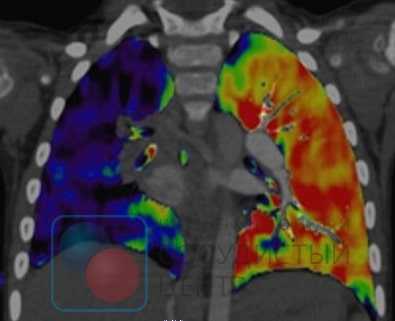

- сцинтиграфию легких (нарушение перфузии крови через легочную ткань говорит об уменьшении или отсутствии кровотока вследствие ТЭЛА)

Сцинтиграфия информативна в 87% случаев. Она демонстрирует дефекты перфузии эмболического генеза - с чёткой очерченностью, треугольной формой и расположением, соответствующим зоне кровоснабжения поражённого сосуда (доля, сегмент). При окклюзии мелких ветвей лёгочной артерии диагностическая ценность снижается.

Вентиляционно-перфузионная сцинтиграфия легких является методом скрининга для исключения хронической тромбоэмболии как причины легочной гипертензии. У больных после тромбоэмболии обнаруживаются дефекты перфузии в долевых и сегментарных зонах при отсутствии нарушений вентиляции. Перфузионная сцинтиграфия исторически стала одним из первых методов обнаружения дефектов перфузии легочной паренхимы при ТЭЛА. Изображения, получаемые при острой ТЭЛА и ХТЭЛГ, существенно различаются. Дефекты перфузии при острой ТЭЛА более четко очерчены и резко контрастируют с нормально функционирующей тканью. При ХТЭЛГ дефекты перфузии очерчены не четко и часто не соответствуют зоне кровоснабжения крупной легочной артерии.